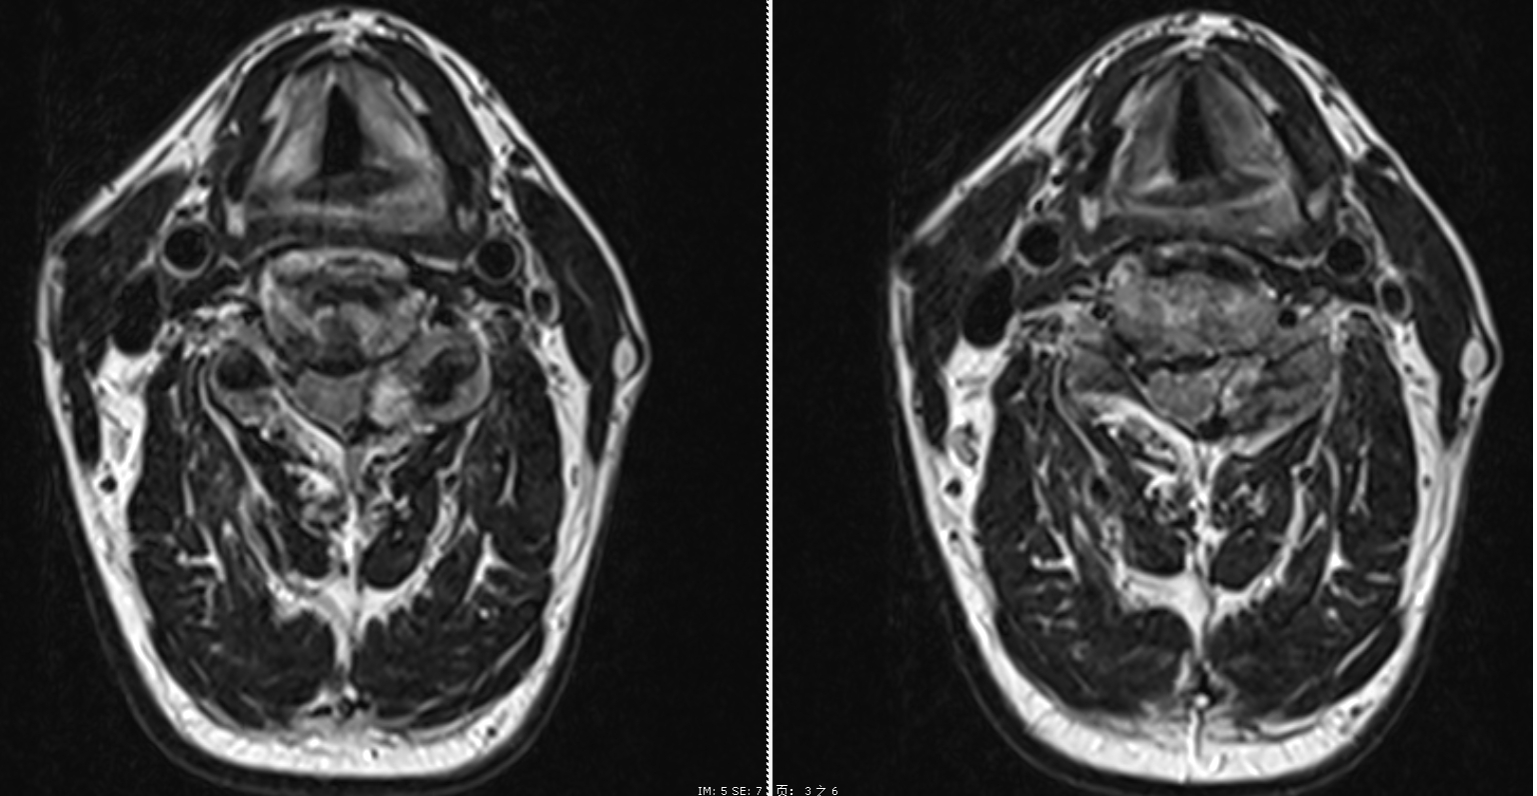

手術過程中,醫療團隊憑借精湛的技術和默契的配合,成功為患者解除了神經壓迫。術后,患者癥狀得到顯著緩解,復查MRI結果顯示脊髓壓迫已完全解除,脊髓膨隆狀態良好。患者術后僅一天便能下床活動,三天后順利出院。術后兩周隨訪,患者的疼痛癥狀已經完全消失,基本恢復正常的日常活動。

術后第一天MRI圖像